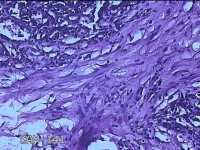

右侧手掌肉芽组织

性别

女

年龄

48岁

临床诊断

手掌开放性损伤

一般病史

右侧手掌肉芽组织增生

标本名称

大体所见

灰白暗红色带皮肤样组织1.3x0.8x0.3cm一块,切面灰白粉红色,质软。

图3